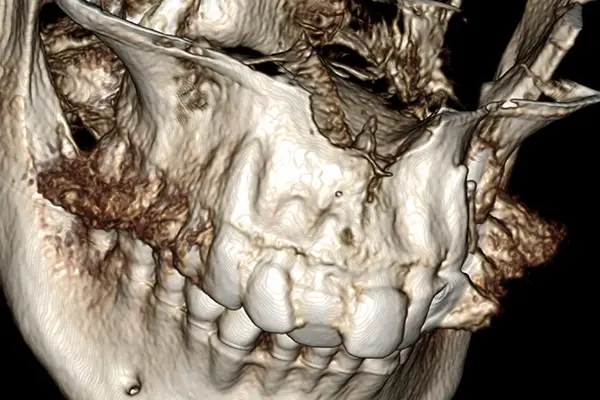

Retreatment of failures from prevention to advanced guided bone regeneration on ailing dental implant

Dr. Giorgio Tabanella